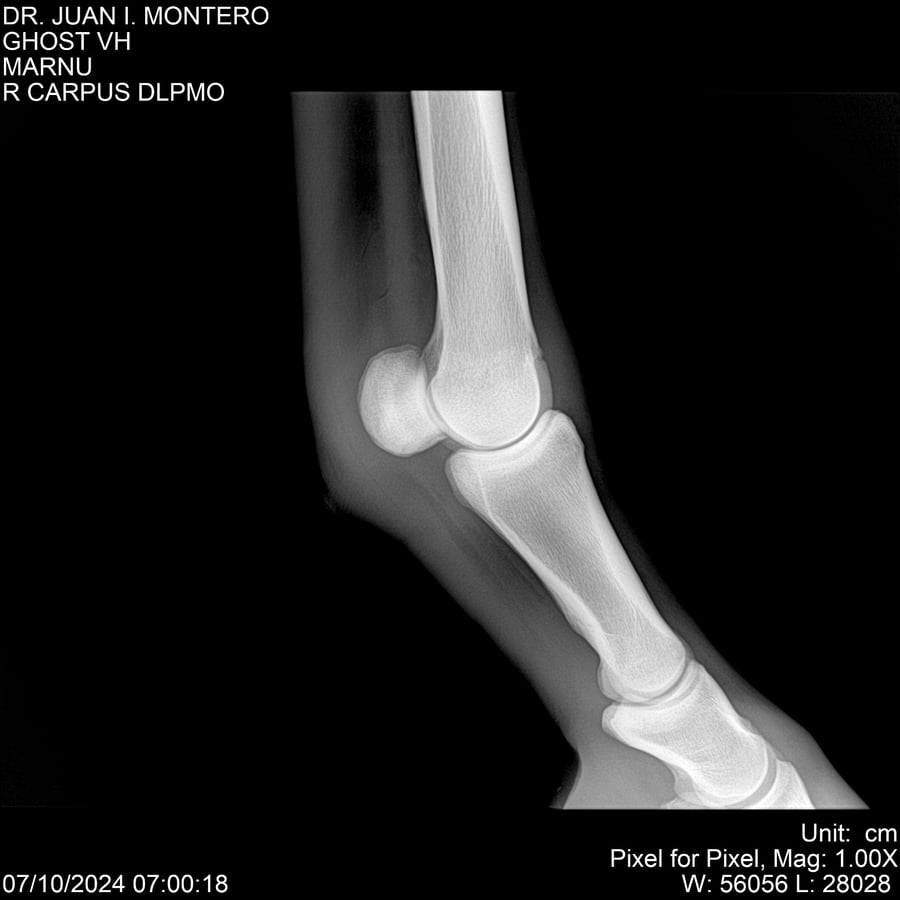

LOTE 15, GHOST VH 🔥 🔥 🔥 Lote Anterior Volver al remate Lote Siguiente Ficha Contacto Montevideo - Ficha del Lote Identificador: #282525 Categoría: Yeguarizos Montevideo - 69 Visualizaciones ClicData Contacto Empresa: Abelenda N. R., Walter Hugo Nombre*: Teléfono* : E-mail* : Mensaje Enviar Registrese gratis Este contenido Exclusivo está disponible sólo para usuarios registrados Ingresar